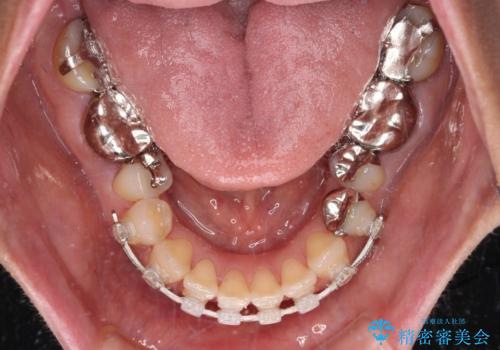

- 矯正装置

- 審美装置

当初はセラミック治療だけを希望されていましたが、上下前歯のデコボコが顕著であったため、セラミッククラウンにて治療する前に再度矯正治療を行った方が仕上がりがきれいになると説明し、再矯正を行うこととしました。

舌突出癖により、上下前歯が突出して離開してしまったため、舌のトレーニングを徹底的に行いました。